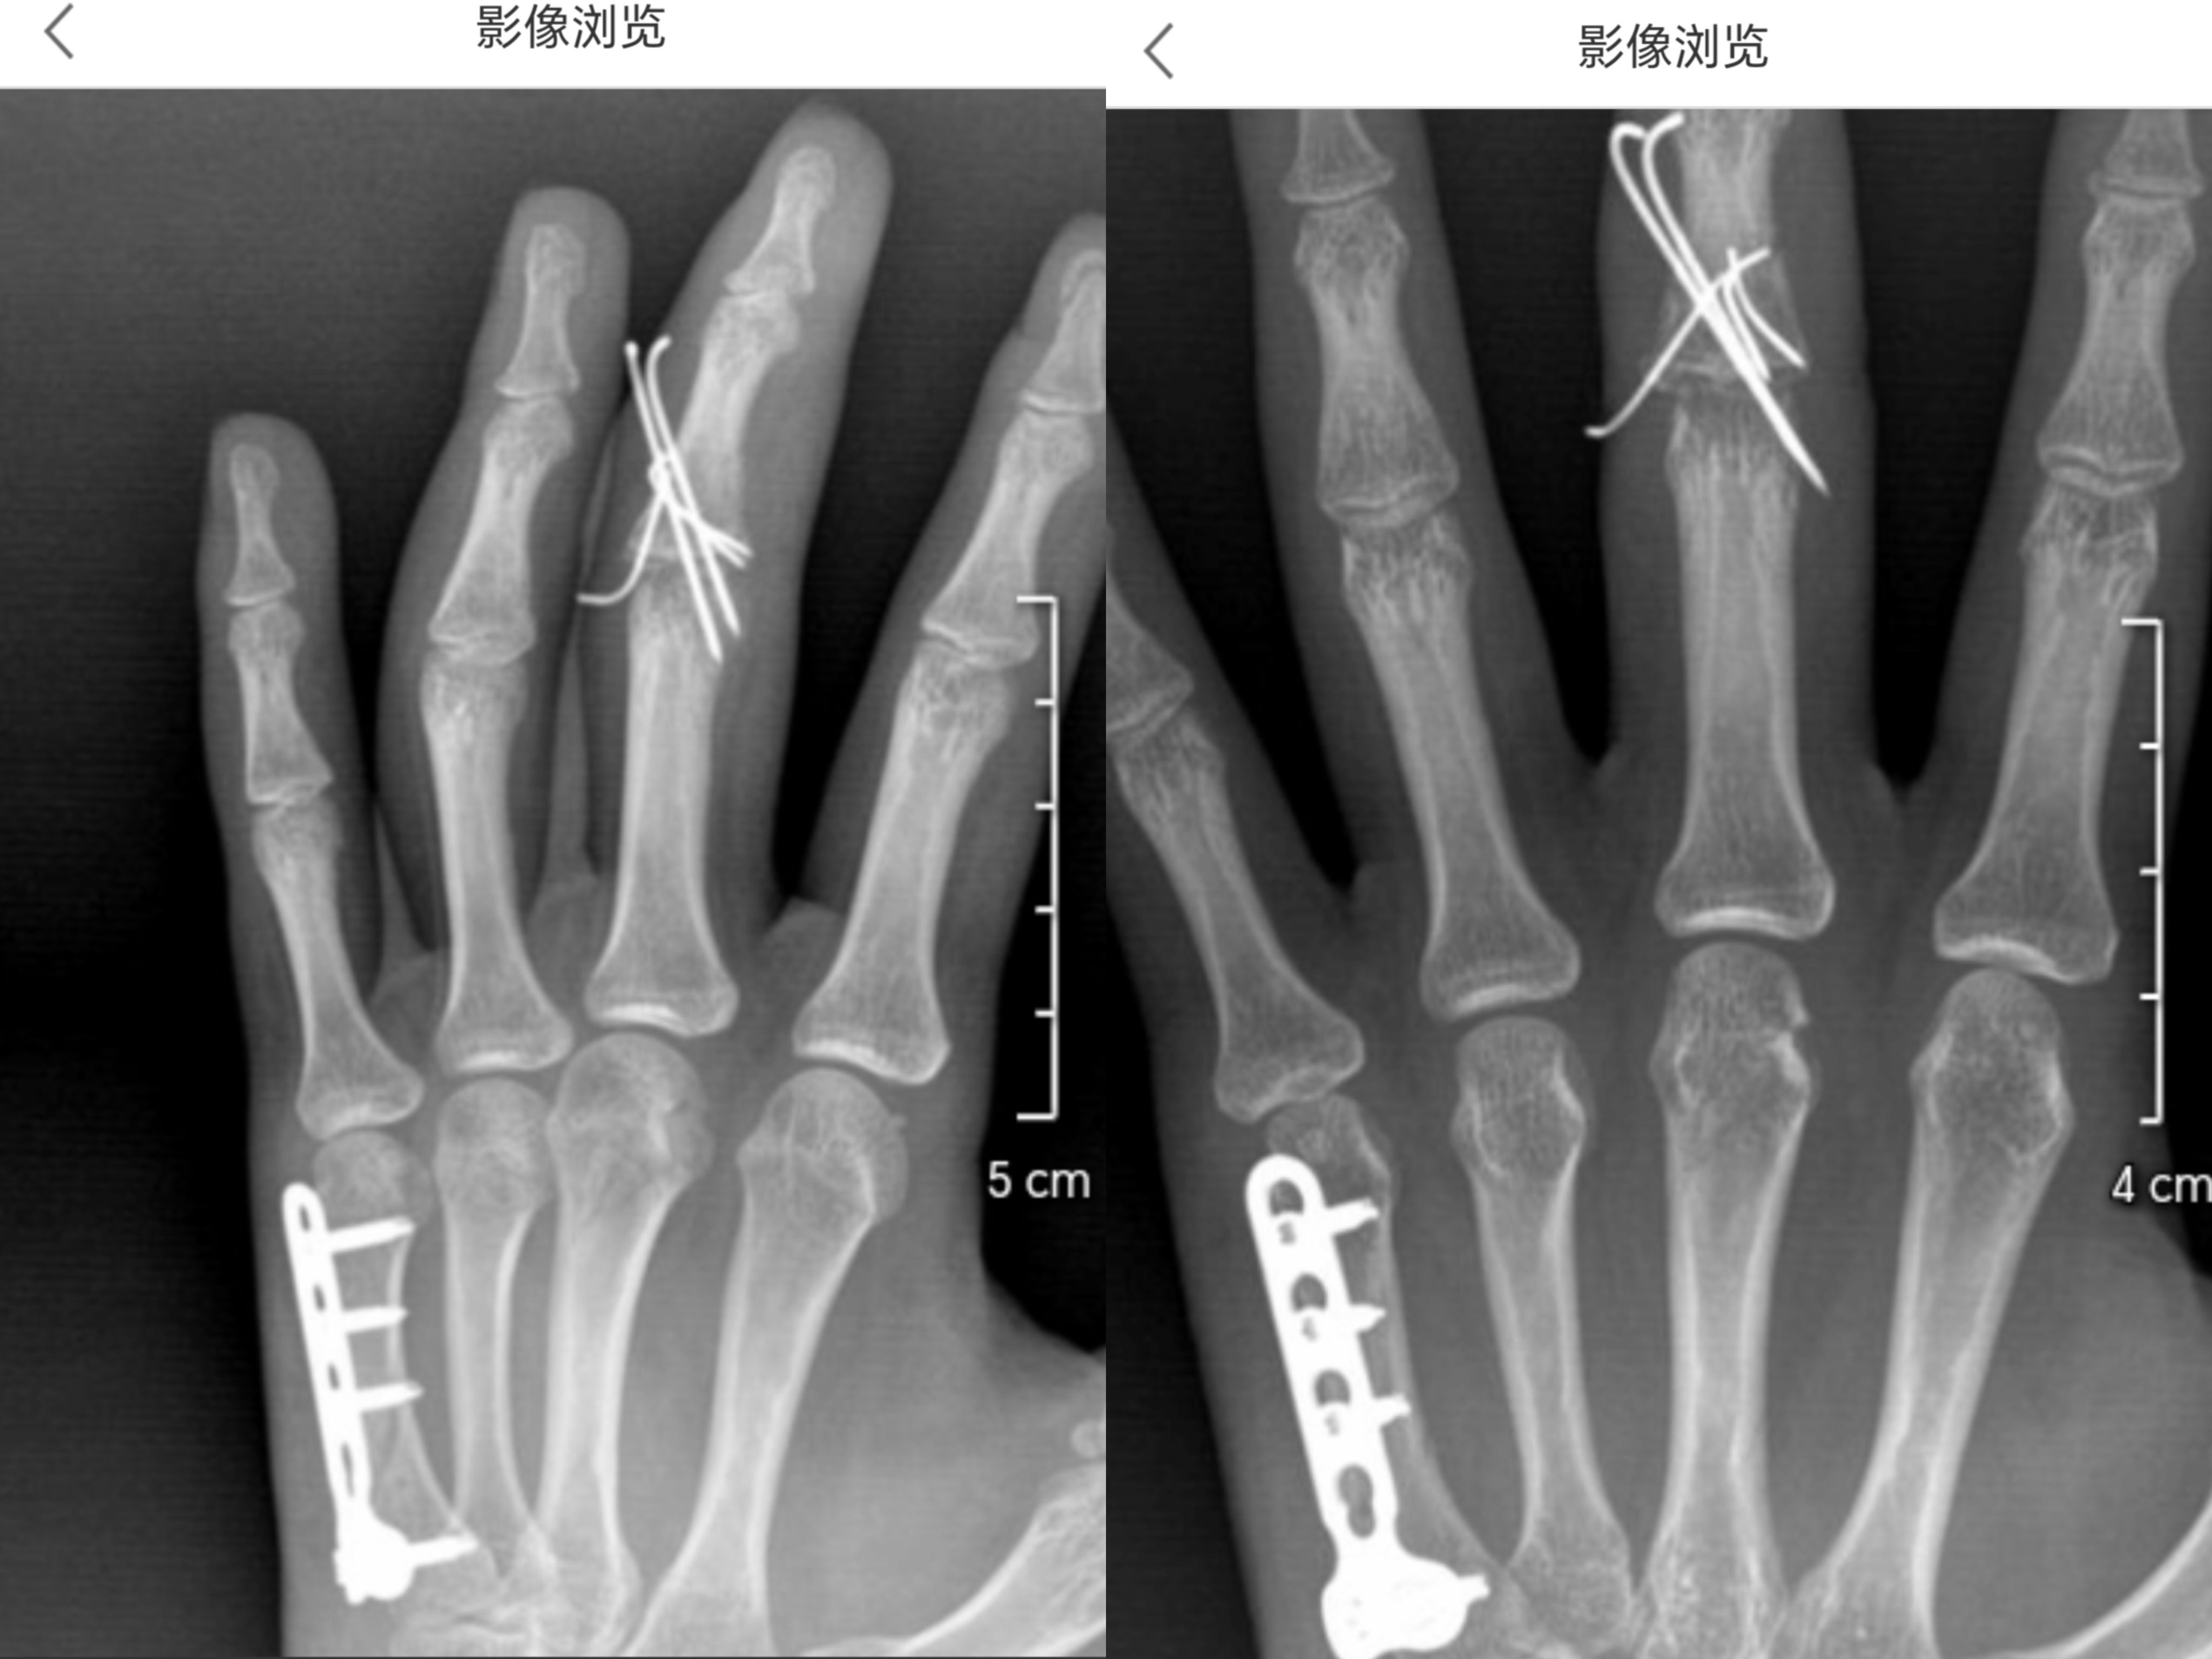

肥哥我今天刚从骨科拆钉回来,第五掌骨打了钢板之后小拇指弯不下来叻,锻炼是得硬掰吗?( ゚∀。)中指中节拆了钉也不太能动,碎成这样以后康复能到啥程度呀

无标题 无名氏 2025-05-21(三)22:27:56 ID:oq5L8xo [举报] No.66130053 管理

>>No.66130032

肥哥这个固定了多久( ゚ 3゚)

也不是硬掰,慢慢来,因为固定期间肌肉不动会萎缩的,另外毕竟前面往里头放不属于身体的东西,肌肉和骨头结构有改变,打钉也打在骨头里,先捏小球啥的轻度锻鍊先( ゚ 3゚)

至于康复到什么程度就是看各人,没有定数的

固定四周拆了2根长钉和石膏,现在六周把钉都拔了。对了当时做手术局麻,还听到医生们哭着说好难拼的骨头( ゚∀。)大家私底下好活泼。

那都听到了,骨头都得拼回去,这生理机能能和本来一样吗( ゚ 3゚)